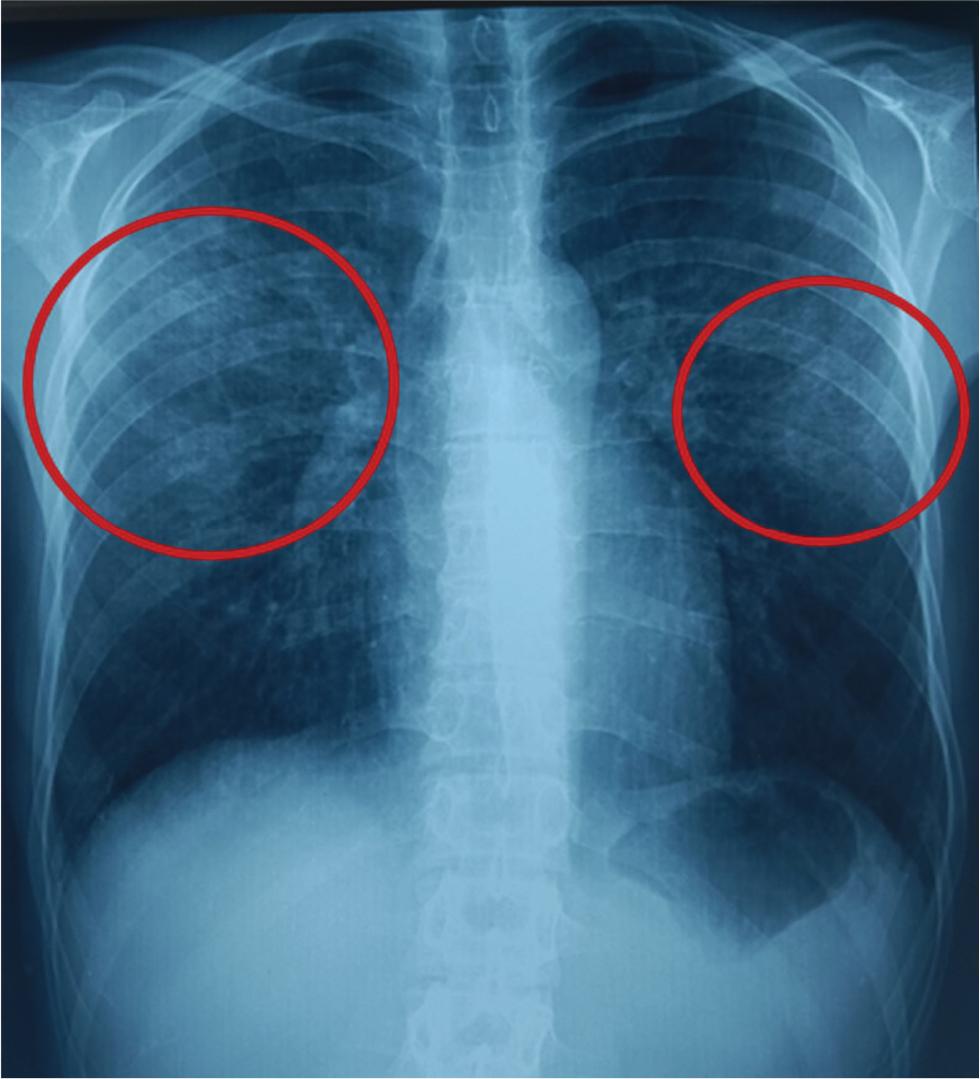

Two days later, the patient returned with recurrent fever and shortness of breath. On examination, his oxygen saturation was 89%, his heart rate was 123 bpm and he appeared mildly lethargic. He was re-admitted and treated with intravenous antibiotics (levofloxacin 500 mg once daily and cefotaxime 1 g three times daily) for 7 days. He was then discharged and referred for a pulmonology outpatient visit, where he presented a month and a half later with persistent dyspnoea (modified Medical Research Council grade 2) and unintentional weight loss. A chest X-ray revealed an interstitial pattern (Figure 2), prompting a repeat CT scan performed in August 2024, approximately 3 months after the initial CT examination, which demonstrated a diffuse interstitial pneumonia pattern, with patchy ground-glass opacities in a mixed central (peribronchovascular) and peripheral distribution, with subpleural sparing. Lesions were predominantly distributed in the upper lobes. The consolidations in the lower lobes had resolved (Figure 3).

Chest X-ray showing an interstitial pattern predominantly involving the mid- and upper-lung zones.